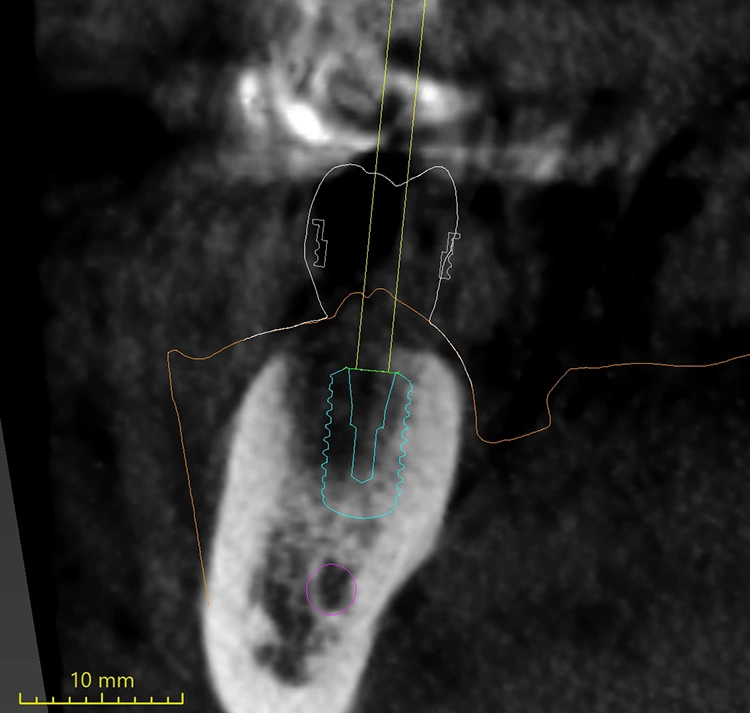

Drei Monate nach der Extraktion des nicht erhaltungswürdigen Zahnes 46 wurde im Januar 2021 eine DVT angefertigt (Abb. 2) und es wurden Ober- und Unterkiefer abgeformt. Für die Planung der Bohrschablonen (Fremdlabor) erfolgte die Digitalisierung der Modelle mit einem Laborscanner im Eigenlabor, anschließend wurden die Daten an den Planungspartner zur Herstellung der Bohrschablonen übermittelt. Dort erfolgte die digitale Vorplanung der Implantatposition und der prothetischen Versorgung mit der Planungssoftware coDiagnostiX (dental wings) (Abb. 3 und 4).